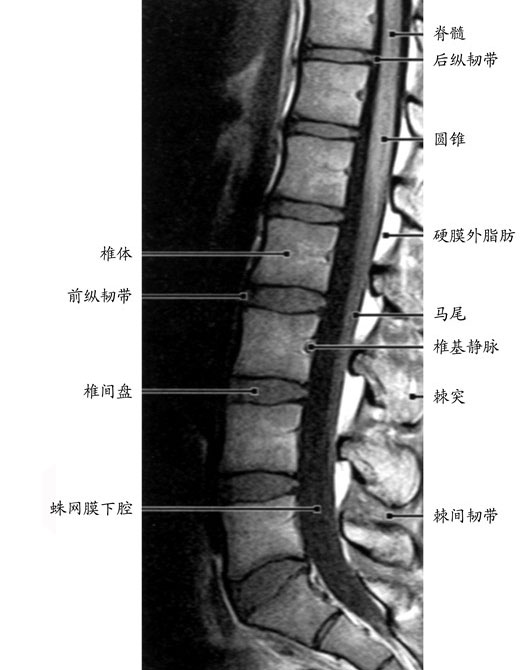

腰4腰5在什么位置图片,腰5骶1的真人位置图片

疼痛多发于下腰椎(最下面的两个部位,即腰4和腰5之间和腰5和骶1之间)

(2)下肢放射性疼痛:由于腰椎间盘突出多发生在腰4,5和腰5骶1椎间隙